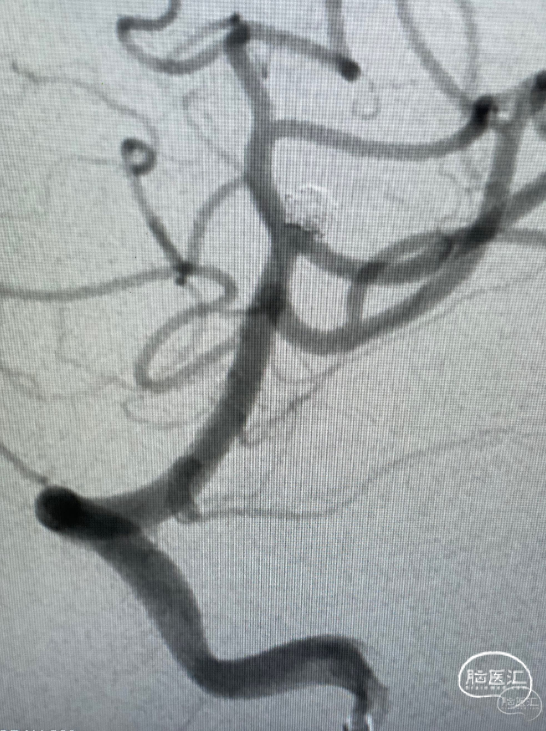

第一台手术结束。开始第二台,一个复发大脑中动脉瘤,复发部位虽然不大,但毕竟是出血动脉瘤,还是远期继续增大再出血的风险。

Lvis jr小支架辅助小弹簧圈栓塞,很好的解决的复发部分。

再次造影,没有动脉瘤的显影了,远期再复发的几率就很小了。